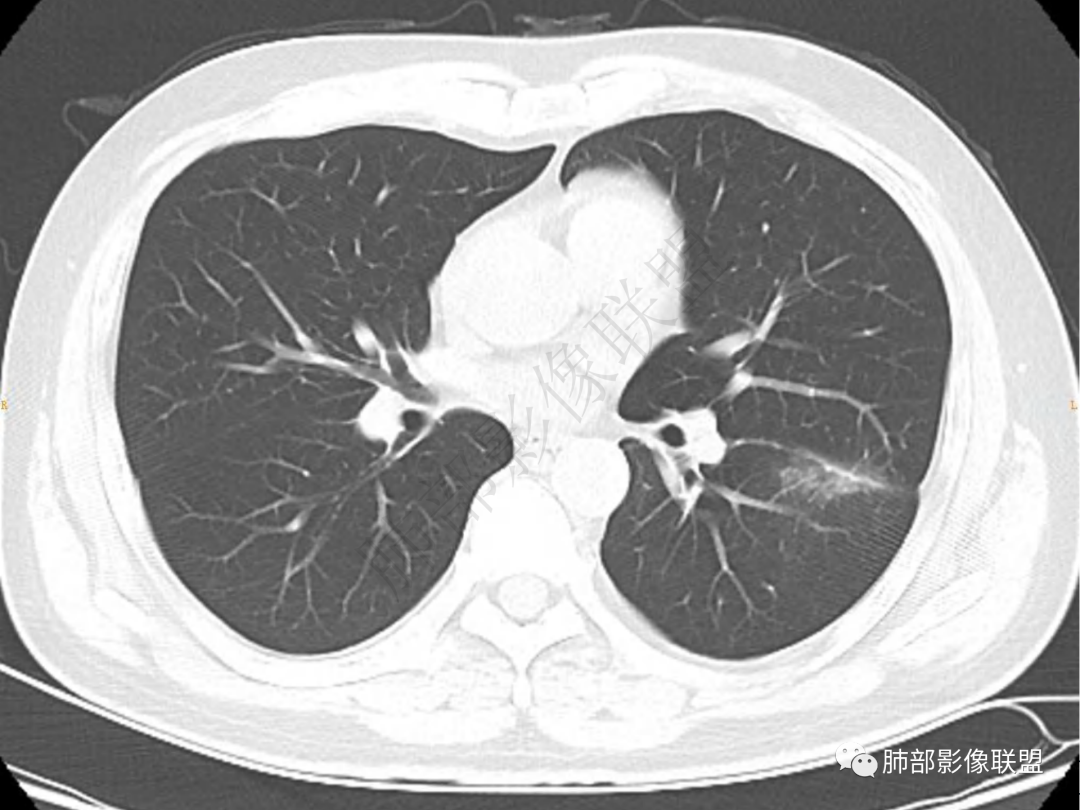

2.左肺下叶团片影,跨背段及内前基底段,实性部分类椭圆形,密度不甚均匀,可见毛刺及棘状突起,未见典型分叶及胸膜凹陷。病灶上下缘可见相应肺段支气管旁进侧出,管壁轻度增厚,未见狭窄阻塞。

3.周边较大范围磨玻璃影,边界相当模糊,小叶增厚明显。注意叶裂另一侧、左肺舌段亦可见磨玻璃影及增厚的小叶间隔。未见明确卫星病灶。

4.实性部分不均匀环形强化并显示一小范围低密度坏死区或空洞。较之肺窗,整体纵隔窗范围较小,提示病灶并不十分密实。抑或为不同时段图像。

5.双肺门及纵隔未见增大淋巴结。未见胸腔积液。